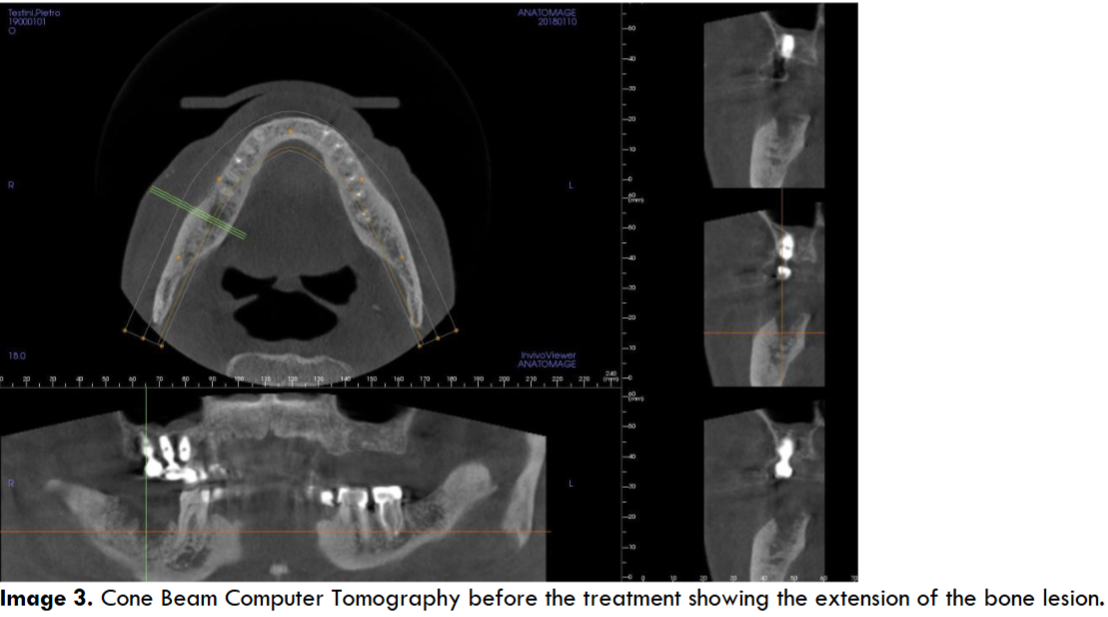

The lesion showed necrotic bone mixed with other parts in rapid growth: the cavity arrived so much deep that the lesion interested the lower alveolar nerve, causing a continuous, severe and burning pain interesting the mandible and radiated to the right ear, causing a worsening of the patient’s quality of life. Since his clinical conditions were very compromised above all for a severe heart failure it was decided to avoid any surgical approach, and the applied therapy was just a local disinfection and antibiotic drugs in case of infection. Moreover the patient used a lot of drugs (furosemide 125 mg twice a day, acetilsalicilic acid 100 mg once a day, Ivabradine 2.5 mg twice a day, Canrenone 50 mg a day, Silodosin 8 mg once a day and pantoprazole 40 mg once a day), and above all he used zolendronic acid (Zometa®) to control the bone metastasis growth derived from the prostatic cancer: this condition increased the risk to have a BRONJ as a postsurgical complication. However, for a continuous worsening of the symptoms and for the several infections of the mandibular lesion we decided, in agreement with his relatives, to surgically remove the gingival lesion cleaning the bone cavity with a conservative approach. To reduce the risk of postsurgical infections and of a bad healing (due to the zolendronic acid and the clinical conditions of the patients) we decided to fill the residual cavity with PRGF®-Endoret® autologous membranes, a particular platelet concentrate that improves and stimulates the healing processes inducing a good tissue regeneration. The Cone Beam Computer Tomography (CBCT) showed the extension of the bone lesion (images 3-4).

Cone Beam Computer Tomography before the treatment showing the extension of the bone lesion.

Cone Beam Computer Tomography before the treatment showing the proximity of the lower alveolar nerve on the right side and the pathologic bone, condition that induced radiated pain from the mandible up to the right ear.